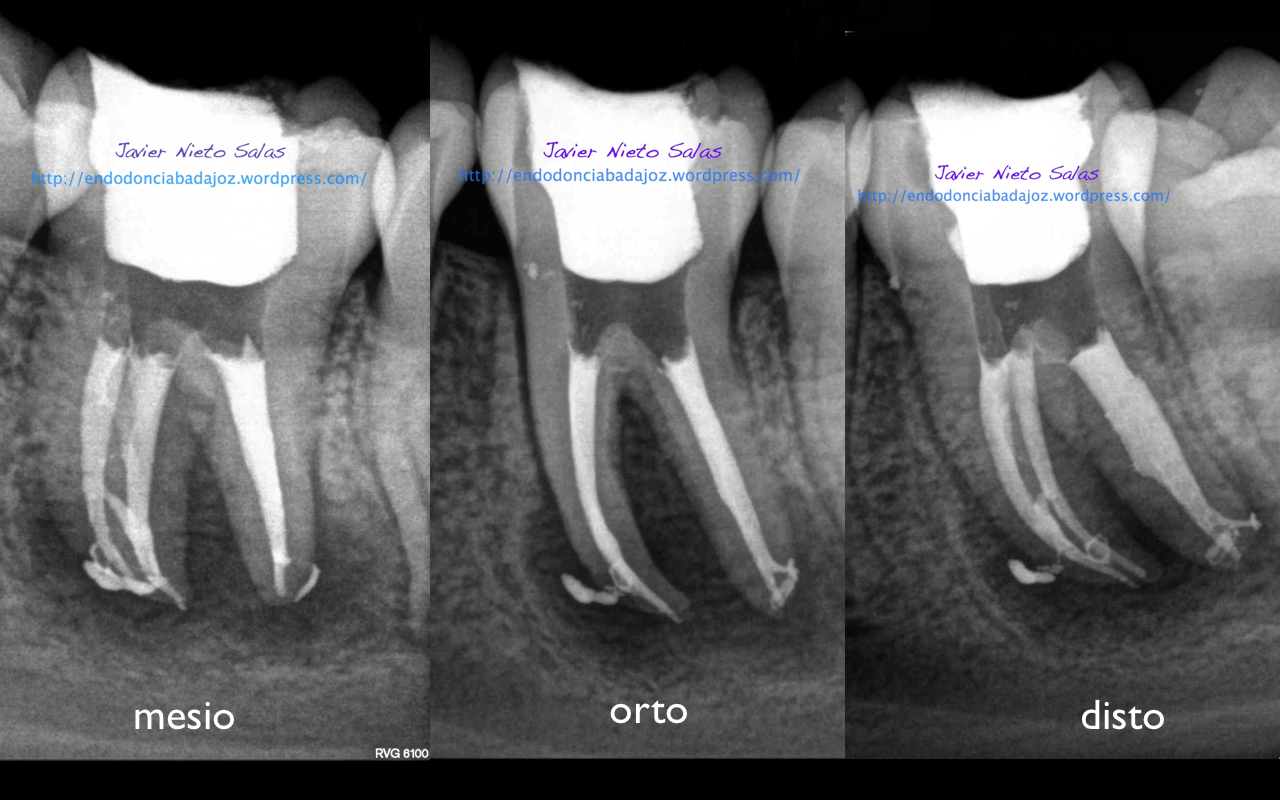

Caso B:

También se llamo a revisión a los 10 meses.

Con respecto a tu pregunta sobre las dos últimas Rx, que son la revisión de las anteriores, de una periodontitis apical crónica de un 4.6, si puedes observar en la radiografía distalizada final, existe un istmo entre ambos conductos, y puede ser que exista un conducto lateral, pero como ya sabemos, existe una gran complejidad anatómica del sistema de conductos. El blog de Ronal Ordinola, es fantástico, y puedes ver esas anatomías en las que piensas en que la endodoncia es un verdadero RETO.